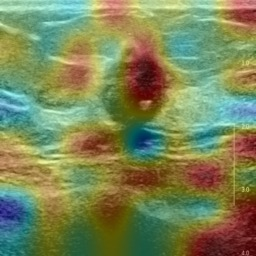

Ultrasonography is an important routine examination for breast cancer diagnosis, due to its non-invasive, radiation-free and low-cost properties. However, it is still not the first-line screening test for breast cancer due to its inherent limitations. It would be a tremendous success if we can precisely diagnose breast cancer by breast ultrasound images (BUS). Many learning-based computer-aided diagnostic methods have been proposed to achieve breast cancer diagnosis/lesion classification. However, most of them require a pre-define ROI and then classify the lesion inside the ROI. Conventional classification backbones, such as VGG16 and ResNet50, can achieve promising classification results with no ROI requirement. But these models lack interpretability, thus restricting their use in clinical practice. In this study, we propose a novel ROI-free model for breast cancer diagnosis in ultrasound images with interpretable feature representations. We leverage the anatomical prior knowledge that malignant and benign tumors have different spatial relationships between different tissue layers, and propose a HoVer-Transformer to formulate this prior knowledge. The proposed HoVer-Trans block extracts the inter- and intra-layer spatial information horizontally and vertically. We conduct and release an open dataset GDPH&GYFYY for breast cancer diagnosis in BUS. The proposed model is evaluated in three datasets by comparing with four CNN-based models and two vision transformer models via a five-fold cross validation. It achieves state-of-the-art classification performance with the best model interpretability.